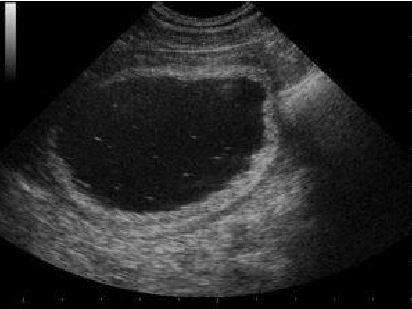

compatibile con una cistite, e la presenza di cristalli in sospensione visibili come dei puntini più

bianchi (iperecogeni), immersi nell’urina di colore nero (anaecogena).